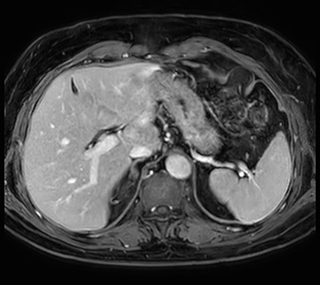

Ascites can be hard to image, but excellent result is obtained with Ingenia Ambition. This high resolution image demonstrates the high quality that can be obtained with VitalEye and the patient just breathing normally. The acquisition time is fast thanks to the accuracy of the respiratory gating with VitalEye** and it also saves the time needed to put a respiratory belt on the patient.

3D T2 with VitalEye

Performed on Ingenia Ambition. FOV 430 mm, voxels 1.3 x 1.3 x3.0 mm, 130 slices, Breath hold 16.6 sec

Using mDIXON provides excellent fat saturation uniformity. No artifacts seen at the edges in these images, while these were quite commonly seen with eTHRIVE on our previous system. Note also the high resolution.

Ingenia Ambition, 3D breath hold, FOV 370 mm, voxels 1.51 x 1.58 x 4.0 mm, 120 slices, scan time 19.6 sec.